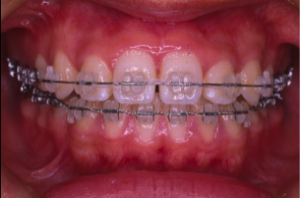

叢生(そうせい)

20歳/女性

悩み:歯がデコボコ

八重歯が押し出されて歯がでこぼこに並んでいる状態

治療期間:約2年4ヶ月

治療前

治療後

奥の歯が倒れて狭くなっている台形の歯列を広げて歯を起こす治療で、奥の歯が見えるようになるUの字型に治しました。

上の歯下の歯、それぞれ2本づつ第一小臼歯を抜歯した治療となりました。

歯を見せて笑えるようになり喜んでもらいました。